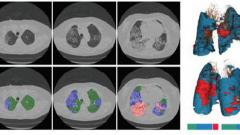

Gustave Roussy, l’hôpital Bicêtre (AP-HP), la startup Owkin et l’Inria (Institut national de recherche en sciences et technologies du numérique) ont allié leurs expertises pour prédire la sévérité de l’infection au coronavirus d’un patient dès le diagnostic, grâce à l’analyse croisée de paramètres cliniques, biologiques et radiologiques par une...

Un nouveau scanner, dit "in the box", vient d’être installé à Gustave Roussy. C’est le deuxième scanner de ce type installé en France. En cette période de crise sanitaire, son arrivée était attendue pour répondre à la demande croissante d’examens d'imagerie, avant que le plateau technique de l'Institut ne soit renforcé dans quelques mois.